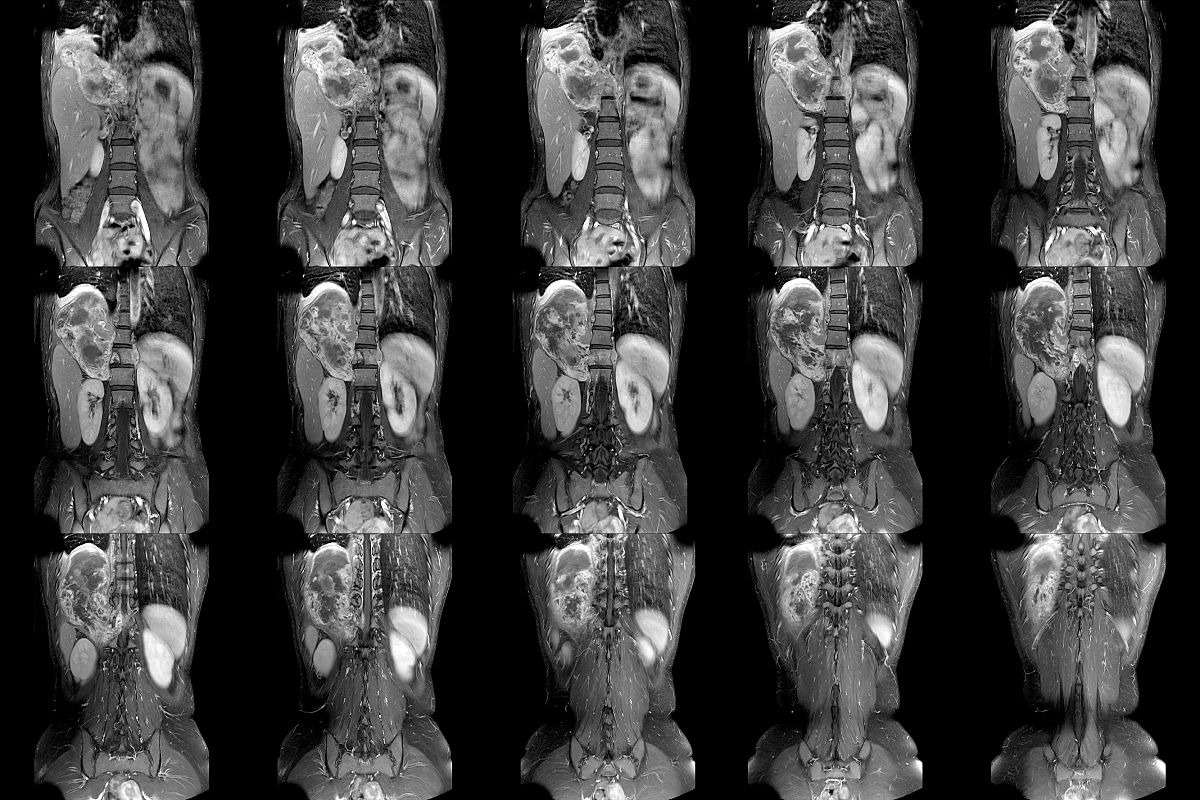

椎体成形术(percutaneous vertebral augmentation, PVA)是一种用于治疗脊柱骨折和椎体压缩性骨折的介入手术。其适应症和禁忌症如下:

1. 脊柱骨折:椎体成形术常用于治疗由骨质疏松、脊柱转移性肿瘤、骨髓瘤等引起的椎体骨折。

2. 椎体压缩性骨折:椎体成形术对于因骨质疏松、骨髓瘤等引起的椎体压缩性骨折也有很好的疗效。

3. 脊柱转移性肿瘤:椎体成形术可以减轻转移性肿瘤对脊柱的破坏,缓解疼痛并恢复脊柱的稳定性。